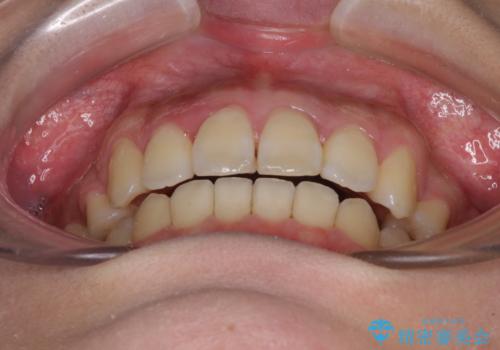

- 八重歯と叢生を気にして来院された患者様です。

上下の前歯が非接触であり、叢生や八重歯が顕著であったため、上顎左右第一小臼歯2本を抜歯して排列することとしました。

抜歯により移動量が多くなるため、ワイヤーや補助装置を活用し、その後インビザラインによる矯正治療を行うこととしました。

元々奥歯に負担のかかる咬み合わせですり減っていたため、仕上がった歯並びでも奥歯が咬んでいないように見えましたが、実際にはしっかりと咬合しており、患者様本人も咬んだ感触に違和感はないとのことでした。